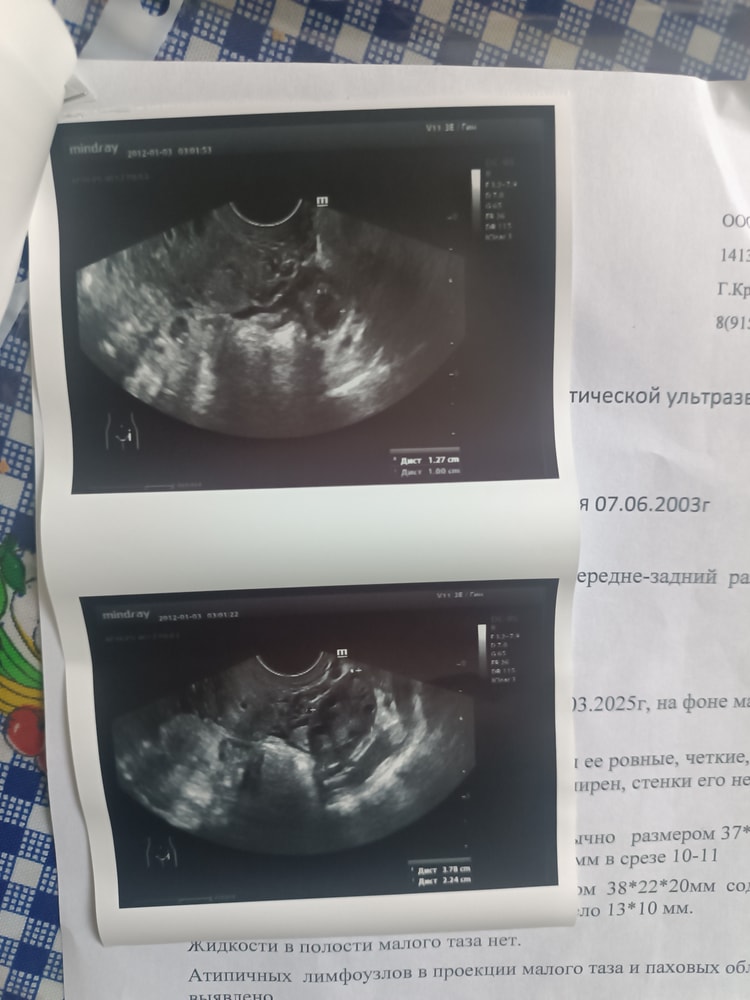

Адель , цикл далеко не стабильный, год назад был выкидыш на 16 неделе и до сих пор ничего не восстановилось. Врачи ставят разные не понятные диагнозы и пытаются их лечить. Чаще всего месячные начинаются после приёма дюфастона. А так мажущие коиичневые выделения, могут идти от 7 до 20 дней. Но тут вроде как произошла овуляция и есть жёлтое тело, надеюсь что все получилось и чуть позже появятся мои две полоски. Планирую сходить на УЗИ ещё к другому врачу потому, что считаю что узист который ставит диагнозы и говорит что у 100% проблемы с гормонами и мне будет тяжело забеременеть во первых не совсем компетентный, а во вторых все таки врач не очень хороший